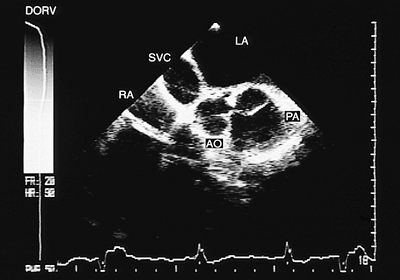

Right Ventricular Double Outlet

In the right ventricular double outlet both great arteries arise mainly or completely from the right ventricle. Any type of A–V connection can coexist. The position of the vessels is variable. When they are side-to-side or the aorta is anterior, the emergence of the vessels is parallel. When the aorta is posterior and right, the great arteries cross in space. Often the underlying anomaly is tetralogy of Fallot with aortic overriding of >50%.

The principal findings observed with transesophageal echocardiography are discussed in the following paragraphs.

Overriding of >50% of the posterior vessel over the interventricular septum is evident in recordings of both transverse and longitudinal planes (Fig. 8.2.52). The connection of both vessels with the right ventricle can be observed in longitudinal images (Figs. 8.2.53 and 8.2.54). When only monoplanar recordings can be obtained, multiple sections at various levels should be visualized to demonstrate that the great arteries are located on the same side of the interventricular septum (Fig. 8.2.55).

FIGURE 8.2.55. Double outlet right ventricle. Transverse plane image. The great arteries, the aorta and the pulmonary artery (AO, PA) have a side-to-side relationship. LA, left atrium; RA, right atrium; SVC, superior vena cava.